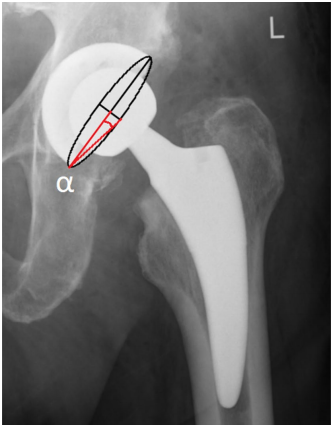

髋臼倾角也称为外展角 (abduction angle)。放射学AI在前后位X线片上测量。它是经坐骨结节线 (transischial line) 与穿过臼杯边缘的线之间的夹角。AI影响活动范围和髋臼部件的磨损。当外展角小于45°,屈曲和外展会减少。另一方面,AI超过45°会减少外展和旋转。当AI超过45°时,髋臼聚乙烯的磨损也会更高。如果没有进一步的研究,无法明确说明AI的安全范围是多少。

髋臼倾角测量。α - 经坐骨结节线与穿过臼杯边缘的线之间的夹角

前倾角 = arc sic (tan α) (注:原文公式表述可能不完整或有误,常见公式为 Anteversion = arcsin (短轴/长轴) 或使用 tan 函数计算角度)α 是椭圆长轴与连接长轴和短轴端点的向量之间的夹角。在平面上,椭圆位于臼杯边缘。

Liaw髋臼前倾角测量法。α — 椭圆长轴与连接长轴和短轴端点的向量之间的夹角。